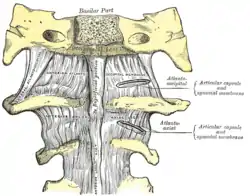

There is a pivot articulation between the odontoid process of the axis and the ring formed by the anterior arch and the transverse ligament of the atlas.

There are three atlanto-axial joints: one median and two lateral:[1]

- The median atlanto-axial joint is sometimes considered a triple joint:[2]

- one between the posterior surface of the anterior arch of atlas and the front of the odontoid process

- one between the anterior surface of the ligament and the back of the odontoid process

- The lateral atlantoaxial joint involves the lateral mass of atlas and axis.[3] Between the articular processes of the two bones there is on either side an arthrodial or gliding joint.

The ligaments connecting these bones are:

The atlantoaxial articular capsules are thick and loose, and connect the margins of the lateral masses of the atlas with those of the posterior articular surfaces of the axis.

Each is strengthened at its posterior and medial part by an accessory ligament, which is attached below to the body of the axis near the base of the odontoid process, and above to the lateral mass of the atlas near the transverse ligament.